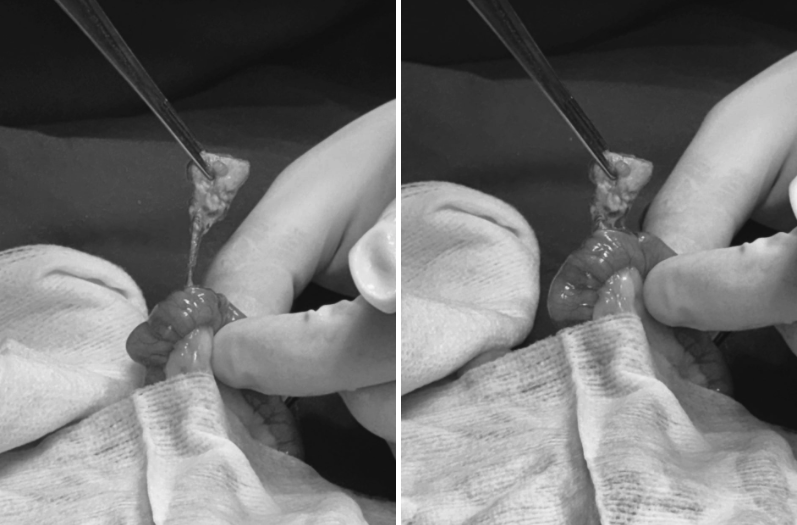

수술 진행

환자는 당일 이물 제거 수술을 진행하기로 결정하였으며, 수술 전 전신 상태 평가에서 마취가 가능한 상태임을 확인했습니다.

위 내 이물제거 수술 사진 / 출처: 라온동물메디컬센터

이물 제거 / 출처: 라온동물메디컬센터

스펀지 형태의 장난감이 소장을 막고 있는 것이 확인되었습니다.

다행히도 장 괴사가 진행되기 전이어서 장절제술까지는 필요하지 않았고, 이물 제거만으로 수술을 마칠 수 있었습니다.